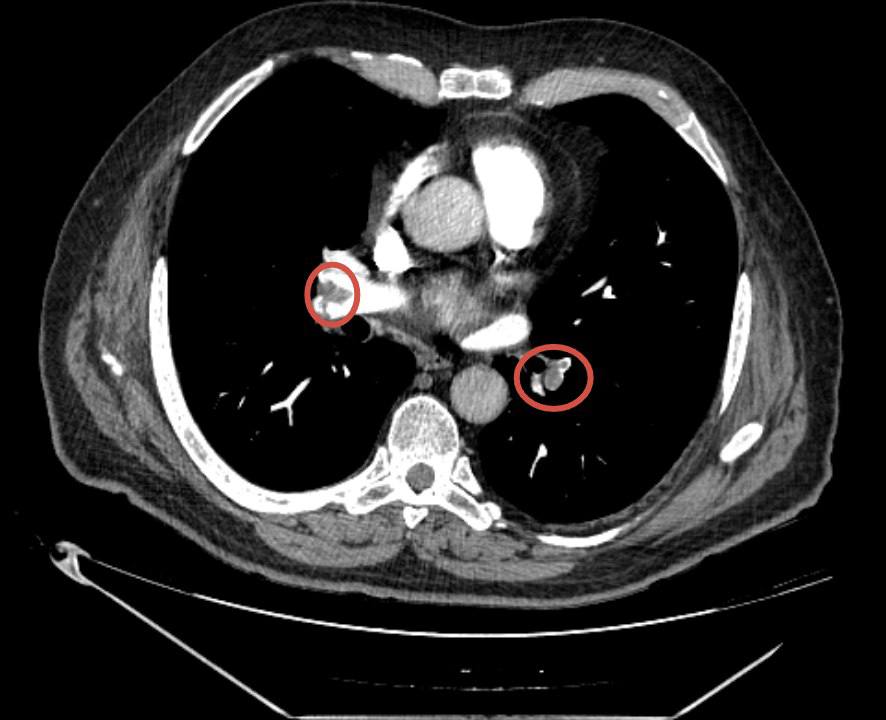

КТ органов грудной клетки показала:

• массивная ТЭЛА,

• поражение ветвей обеих лёгочных артерий,